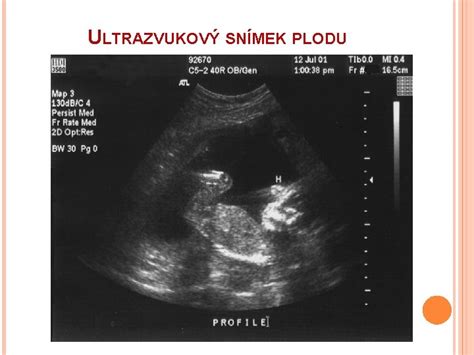

- Zamlčaný potrat: Tento typ potratu je úplne bezpríznakový. Žena si nemusí byť vedomá straty plodu, pričom jej prítomnosť zistí až lekár počas bežného ultrazvukového vyšetrenia, keď zaznamená chýbajúci pulz dieťatka.